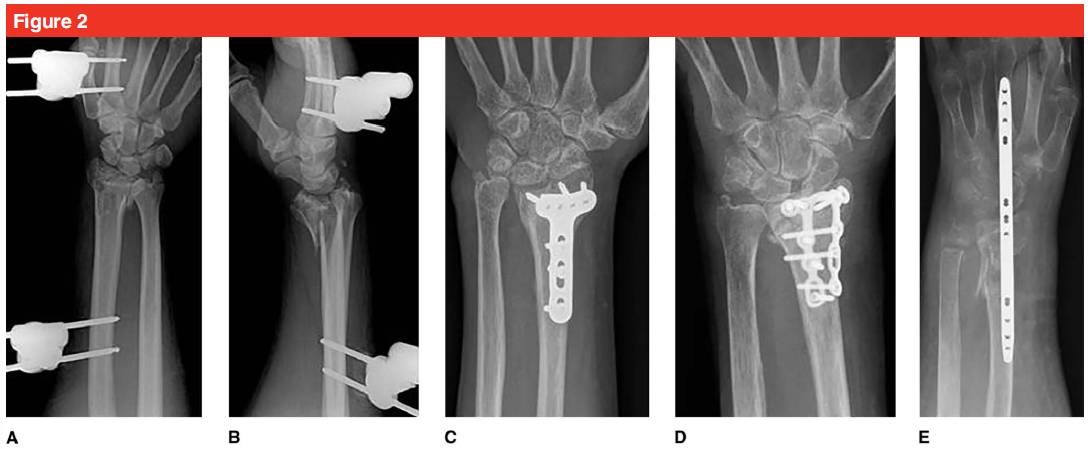

Варианты хирургического лечения пожилых пациентов с переломами дистального отдела лучевой кости включают: закрытую репозицию и наружную фиксацию, чрескожную фиксацию спицами Киршнера, открытую репозицию, фиксацию ладонной/дорсальной запирающей пластиной и фиксацию дорсальной мостовидной пластиной (см. рис. 2).

Другой тип открытой репозиции и фиксации дорсальной пластиной в основном используется для лечения внутрисуставных переломов.Он может уменьшить суставную поверхность под прямым углом зрения, не обнажая ткань связки на ладонной стороне лучезапястного сустава, снижая риск последующей нестабильности лучезапястного сустава.Если вовлечен перелом ладонной полулунной кости, его необходимо иммобилизовать.Для пациентов с переломом диафиза лучевой кости или множественными травмами можно использовать встроенную тракционную пластину для достижения репозиции путем восстановления связок.В то же время тракционная пластина также подходит для репозиции и фиксации оскольчатых и остеопоротических переломов дистального отдела лучевой кости.Пластину сняли через 12 недель после операции, при этом удалось добиться хорошего клинического терапевтического эффекта.

Ладонная блокирующая пластина может уменьшить радиальное укорочение и наклон ладонной кости, а частота осложнений снижается.По сравнению с дорсальной пластиной сила захвата пораженной конечности может быть значительно улучшена в течение 6 месяцев после операции, а функция и боль могут быть улучшены.Такие осложнения, как повторное смещение дорсальной фиксации пластины и раздражение сухожилия разгибателя пальцев, возникают в 30% случаев.Фиксирующий эффект ладонной пластины также лучше, чем у спицы Киршнера или внешнего фиксатора.